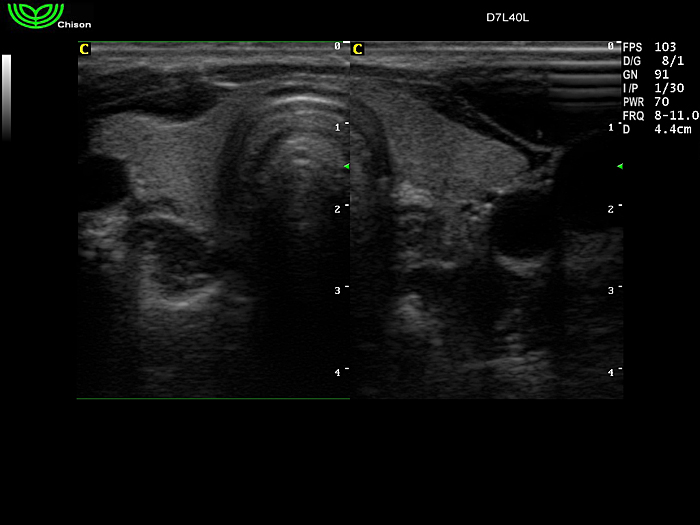

D7L40L 7.5МГц, линейный.

4.0МГц – 13.0 МГц. Применения: грудь, малые органы, нервы, сосуды, венозная катетеризация, мышцы и скелет, управление биопсией. |